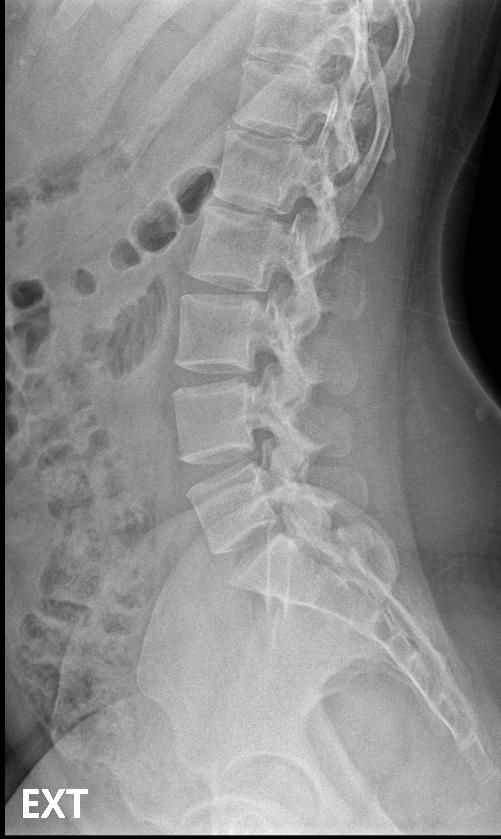

척추분리증인가요??(엑스레이 있어요)

한 병원에서는 척추분리증이라고 하고 한 병원에서는 척추분리증이 아니라고 해서요. 혹시 아래 사진에서 척추분리증 소견이 보이는 사진이 있나요??

여기까지가 a병원에서 찍은 사진이고 아래가 b병원에서 찍은 사진이에요!

• 3번 째 사진

A병원 세번째 사진의 아래 부위에 척추분리증이 있는게 맞습니다.

B병원 사진에서는 비교적 흐리게 보이지만 잘 보면 B병원 엑스레이에서도 같은 부위에 분리증을 확인할 수 있습니다.

두 사진을 비교해서 보았을 때 큰 문제가 있어 보이지는 않으며 엑스레이상 척추분리증 진단이 어렵거나 애매한 경우에는 추가적인 검사 MRI를 통해 진단을 받아보시는 것도 방법이라고 생각합니다.

제가볼때 엑스레이상에 분리증은 보이지않지만 각도에따라 그리고 기계에따라서 달라질수있으니 정확하게 하고싶다면 MRI검사를 추천합니다 감사합니다~

두가지 사진을 비교해보았을 때, 크게 특징적인 것이 관찰되지는 않습니다. 척추분리증을 진단하는 것은 임상증상과 영상검사를 통한 구조적 이상을 확인하는데요, 정확한 검진을 위해서는 ct나 mri같은 검사를 고려하시거나, 척추질환을 전문적으로 진단하는 병원급 의료기관에 방문해보시는 것도 고려해보시면 좋겠습니다.